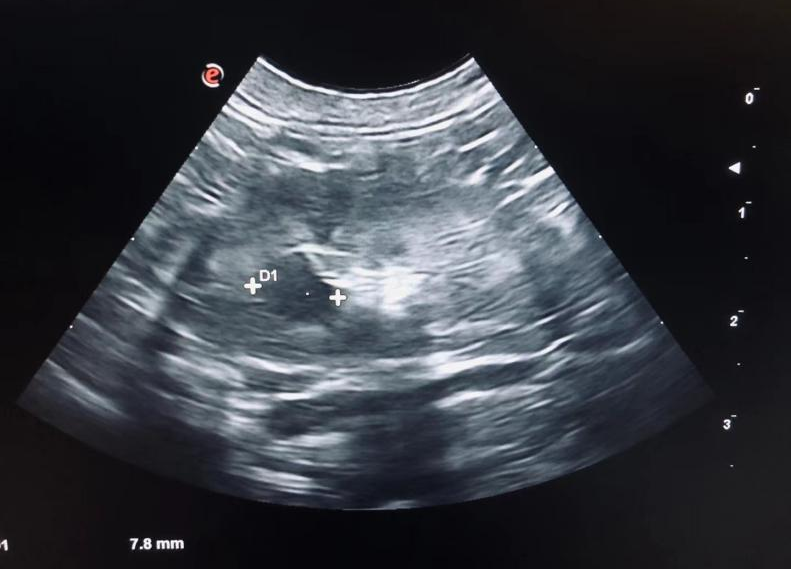

多囊肾影像▲

多囊肾:遗传病,造成肾脏上囊肿形成。这些囊在出生时即存在,非常小,随着时间增长变大,压迫肾脏,造成肾脏疾病。